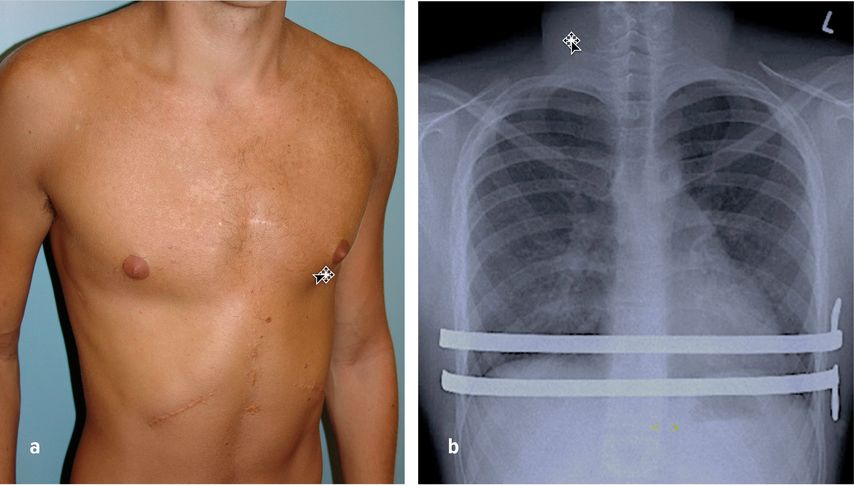

Abb. 7: a) Postoperatives Resultat nach erweiterter Trichterbrustkorrektur, b) ap. Röntgenbild, wo zwei PSI®-Stützplatten zur Korrektur der Trichterbrust verwendet wurden. Die integrierten Stabilisator-Flügel liegen links angepasst am Thorax